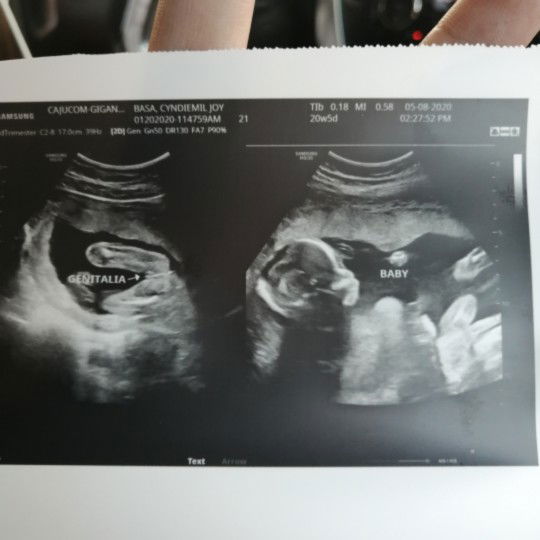

Last 2 weeks ago, nagpost din po ako dito mga mi. 2x nako nag pa tvs pero wala pading baby. Base sa lmp ko dapat 11 w and 4 days na ako today. Pero nagbalik ako sa ob ko nung june 2, and heres the update . NAG SHRINK NA DAW PO YUNG GEST SAC KO. NAGTATAKE NA DIN PO AKO NG MGA MEDS PAMPADUGO. PERO WALA PADIN PONG EFFECT SAKIN. WALA PARIN KAHIT NA ANONG PAIN AND EVEN BLEEDING. #advicepls #pleasehelp #bantusharing #FTM #respect_post #preganancyjourney

WALA NA PO BA TALAGANG CHANCE TO? UMAASA PA DIN PO AKO. LAST TWO WEEKS AGO NAGPA TVS AKO, AND 5WEEKS PALANG DAW AKO BASE SA ULTRASOUND, GESTATIONAL SAC PALANG AND WALA PANG BABY THEN SABI NG OB KO WAIT KAMI NG ANOTHER 2 WEEKS ULIT KUNG LILITAW SI BABY. THEN KAHAPON CHECK UP KO ULIT AND TVS WALANG BABY, WALANG EMBRYO. YUN PADIN YUNG SAC LANG YUNG ANDUN. PWEDENG BLIGHTED OVUM NA DAW AKO. WALA NA BA TALAGANG CHANCE TO😭😭 ##pleasehelp #advicepls